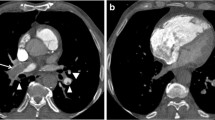

An 18-year-old girl with a history of tetralogy of Fallot and an additional conoventricular septal defect into inlet septum had a lateral tunnel fenestrated Fontan procedure performed at 1 year of age. When the girl developed shortness of breath, she underwent CTPA at an outside hospital for possible PE. At that hospital, CT images were interpreted as PE in the bilateral main pulmonary arteries (Fig. 3). The girl was subsequently transferred to our hospital for further evaluation.

An 18-year-old girl with complex congenital heart disease who had undergone a lateral Fontan procedure. CTPA was performed for evaluation of PE when she presented with shortness of breath. a Enhanced axial CT image obtained at an outside hospital demonstrates a filling defect in the right (arrow) and left (curved arrow) main pulmonary arteries. b Subsequently obtained enhanced CT image shows delayed but homogeneous contrast enhancement within the right (arrow) and left (curved arrow) main pulmonary arteries without evidence of PE

Upon admission to our hospital, the outside hospital CT images (Fig. 3) were reviewed by a pediatric cardiac radiologist and pediatric chest radiologist. Further investigation of the girl’s outside hospital CTPA protocol revealed a single contrast agent injection via a right upper-extremity vein for the CTPA study. The pediatric radiologists and cardiologist taking care of this patient concluded in consensus that filling defects observed in the bilateral main pulmonary arteries observed in the outside hospital CT images might have resulted from incomplete opacification of the contrast agent rather than a real PE. Because of the serious need for clarification of a possible large PE, the girl underwent a repeat CTPA study with a 64-slice MDCT scanner (Sensation 64; Siemens Medical Solutions, Erlangen, Germany) at our institution. CT parameters included 0.6-mm collimation with weight-based low-dose tube current and kilovoltage, high-speed mode, and a pitch of 1.5. Simultaneously, 80 ml of contrast agent (Optiray-320) was administered via a right lower-extremity vein using a power injector at a flow rate of 3 ml/s and 40 ml of contrast agent was administered via a right upper-extremity vein by hand injection at a flow rate of approximately 2 ml/s. The monitoring scan was set at the level of the Fontan pathway at the level of the main pulmonary artery bifurcation. Initial CT scanning was performed 50 s after contrast agent injection. Delayed-phase CT images were then obtained approximately 3 min after the initial contrast agent administration.

Initial repeat CT images demonstrated inhomogeneous contrast enhancement in the bilateral main pulmonary arteries that was less prominent than findings seen on the outside hospital CT images. However, delayed repeat CT images showed much improved homogeneous contrast enhancement within the bilateral main pulmonary arteries without PE (Fig. 3). The absence of PE in the bilateral main pulmonary arteries was confirmed on echocardiography. The girl became asymptomatic after overnight observation and was discharged home the following day.